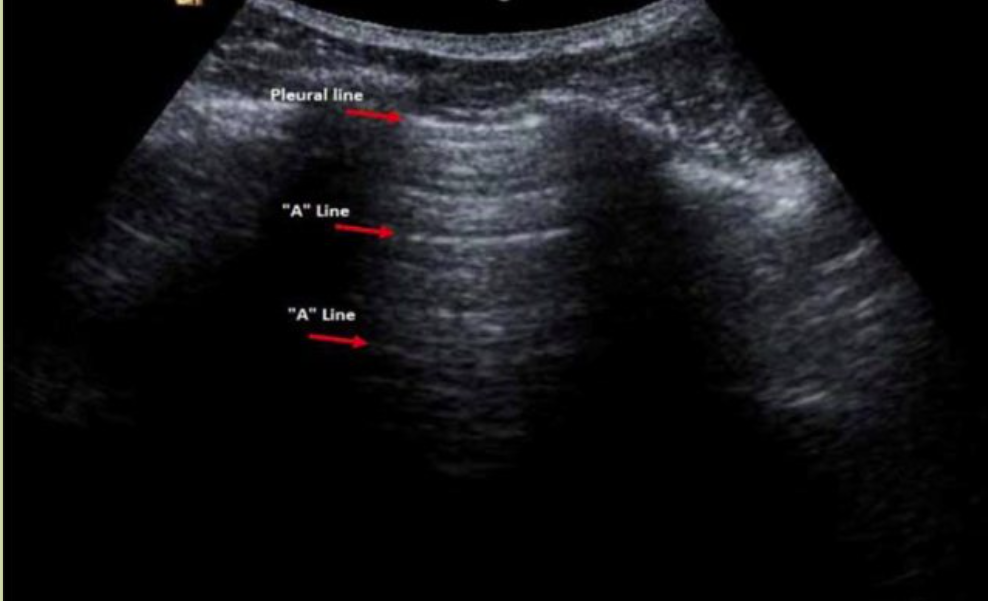

A 线

为水平伪像,指平行于胸膜线的多个短线状强回声,是声波在胸膜处发生的混响效应,其间距相等

A-线系当声束与胸膜垂直时,因混响伪像形成多重反射而产生的一种与胸膜线平行的线性高回声,位于胸膜线下方,超声下呈一系列与之平行的光滑、清晰、规则的线性高回声,彼此间距相等,回声由浅入深逐渐减弱至消失。

正常肺脏超声影像学特点

新生儿正常肺组织在超声下呈低回声。在B型超声下,胸膜线与A-线均呈清晰、光滑、规则的线性高回声(光滑、清晰、规则),彼此等间距平行排列,由肺野浅部入深A-线回声逐渐减弱至消失;无(出生3~7 d后)或可有少数几条B线(生后3~7 d内),但无AIS、胸腔积液和肺实变等超声征象;在实时超声下可见肺滑,在M型超声下则表现为沙滩征